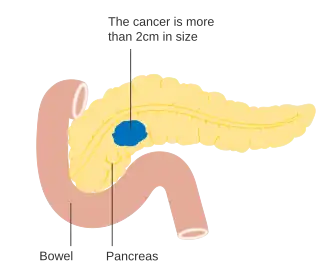

Cancros exócrinos

A determinação do estágio do cancro do pâncreas é geralmente realizada após uma TC.[27] O sistema mais amplamente utilizado de classificação de cancro do pâncreas é o da autoria do American Joint Committee on Cancer (AJCC) em co-autoria com a União Internacional Contra o Cancro (UICC). O sistema AJCC-UICC determina quatro estádios principais, desde o inicial até doença avançada, com base na classificação TNM — tamanho do tumor, grau de propagação para os nódulos (ou gânglios) linfáticos e metástases à distância.[41]

Para auxiliar a decisão sobre a melhor forma de tratamento, os tumores também são divididos em três categorias genéricas com base na possibilidade aparente da remoção cirúrgica. Desta forma, os tumores podem ser considerados "ressecáveis", "marginalmente ressecáveis" ou "irressecáveis".[42] Quando a doença se encontra nos estádios iniciais (estádios AJCC-UICC I e II), sem se ter propagado para vasos sanguíneos de grande dimensão ou para órgãos à distancia, como o fígado ou os pulmões, geralmente é possível realizar a ressecção do tumor, desde que o paciente esteja disposto e apto a submeter-se a esta operação complexa.[11] O sistema AJCC-UICC permite distinguir entre tumores de estádio III que sejam "marginalmente ressecáveis" (em que a cirurgia é tecnicamente viável porque as artérias celíaca e mesentérica superior ainda se encontram livres) e tumores que sejam "irressecáveis" (devido a doença localmente mais avançada). Nos parâmetros da classificação TNM, estes dois grupos correspondem a T3 e T4, respetivamente.[3]

No caso dos denocarcinomas pancreáticos já avançados ou com metástases, que juntos representam 80% dos casos, os diversos ensaios recentes que compararam os regimes de quimioterapia demonstraram uma melhoria no tempo média de sobrevivência, embora não seja superior a um ano.[2][66] Por exemplo, nos Estados Unidos, a taxa de sobrevivência ao quinto ano era de 2% entre 1975 e 1977, melhorando para 4% entre 1987 e 1989 e para 6% entre 2003 e 2009.[36] Nos restantes 20% de casos de adenocarcinoma pancreático com diagnóstico localizado e de pequeno crescimento (<2 cm e estágio T1), cerca de 20% dos norte-americanos sobrevive para além dos cinco anos.[15]